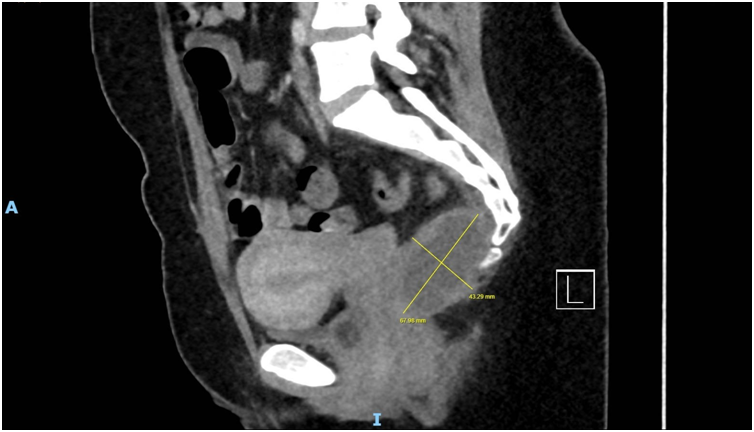

Imaging via MRI and CT demonstrated a complex, encapsulated lesion with peripheral enhancement and restricted diffusion. Multidisciplinary evaluation suggested a congenital epidermoid or duplication cyst. Given the absence of malignancy and surgical complexity, a conservative management strategy was adopted.

Figure 4: Figure 4 Duplication cyst 2020 sagittal plane

Figure 6: Figure 6 Duplication cyst 2025 sagittal plane